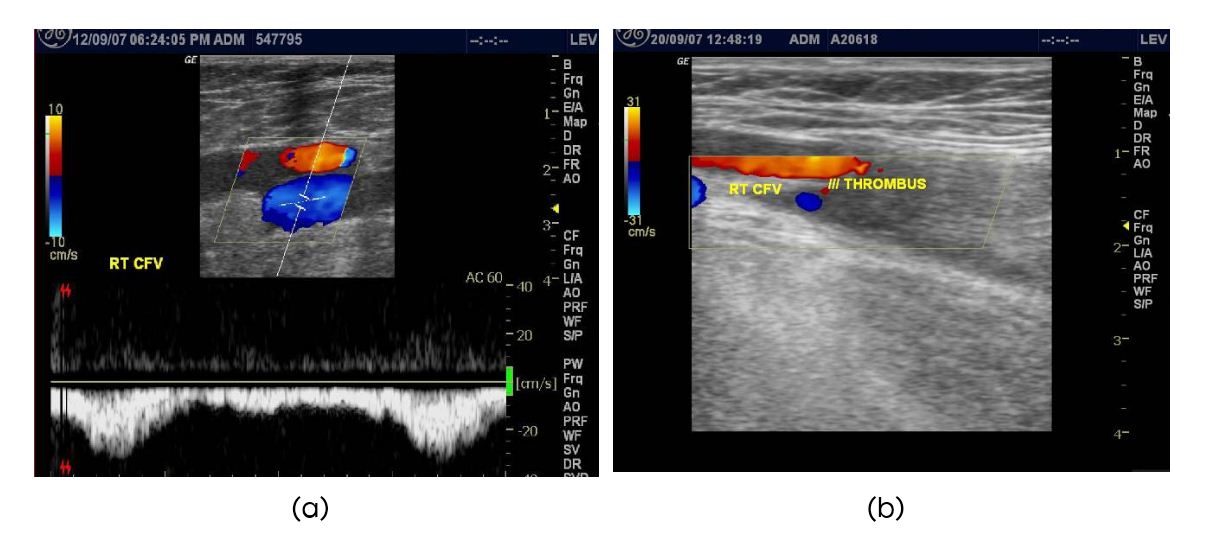

In this study 6 patients developed symptomatic DVT. All were diagnosed and confirmed by color doppler (Figure 1).

Figure 1: Color doppler (a) Preoperative doppler, (b) Early post-operative doppler showing thrombus in the right CFV.

Three patients developed DVT in the early postoperative period (4-13 days). Three patients developed DVT in the late postoperative period (28-42 days). Average time of presentation of DVT was 19.67 days. One patient in our study sample (1.06%) developed non-fatal pulmonary embolism after late onset DVT on the 35th day.